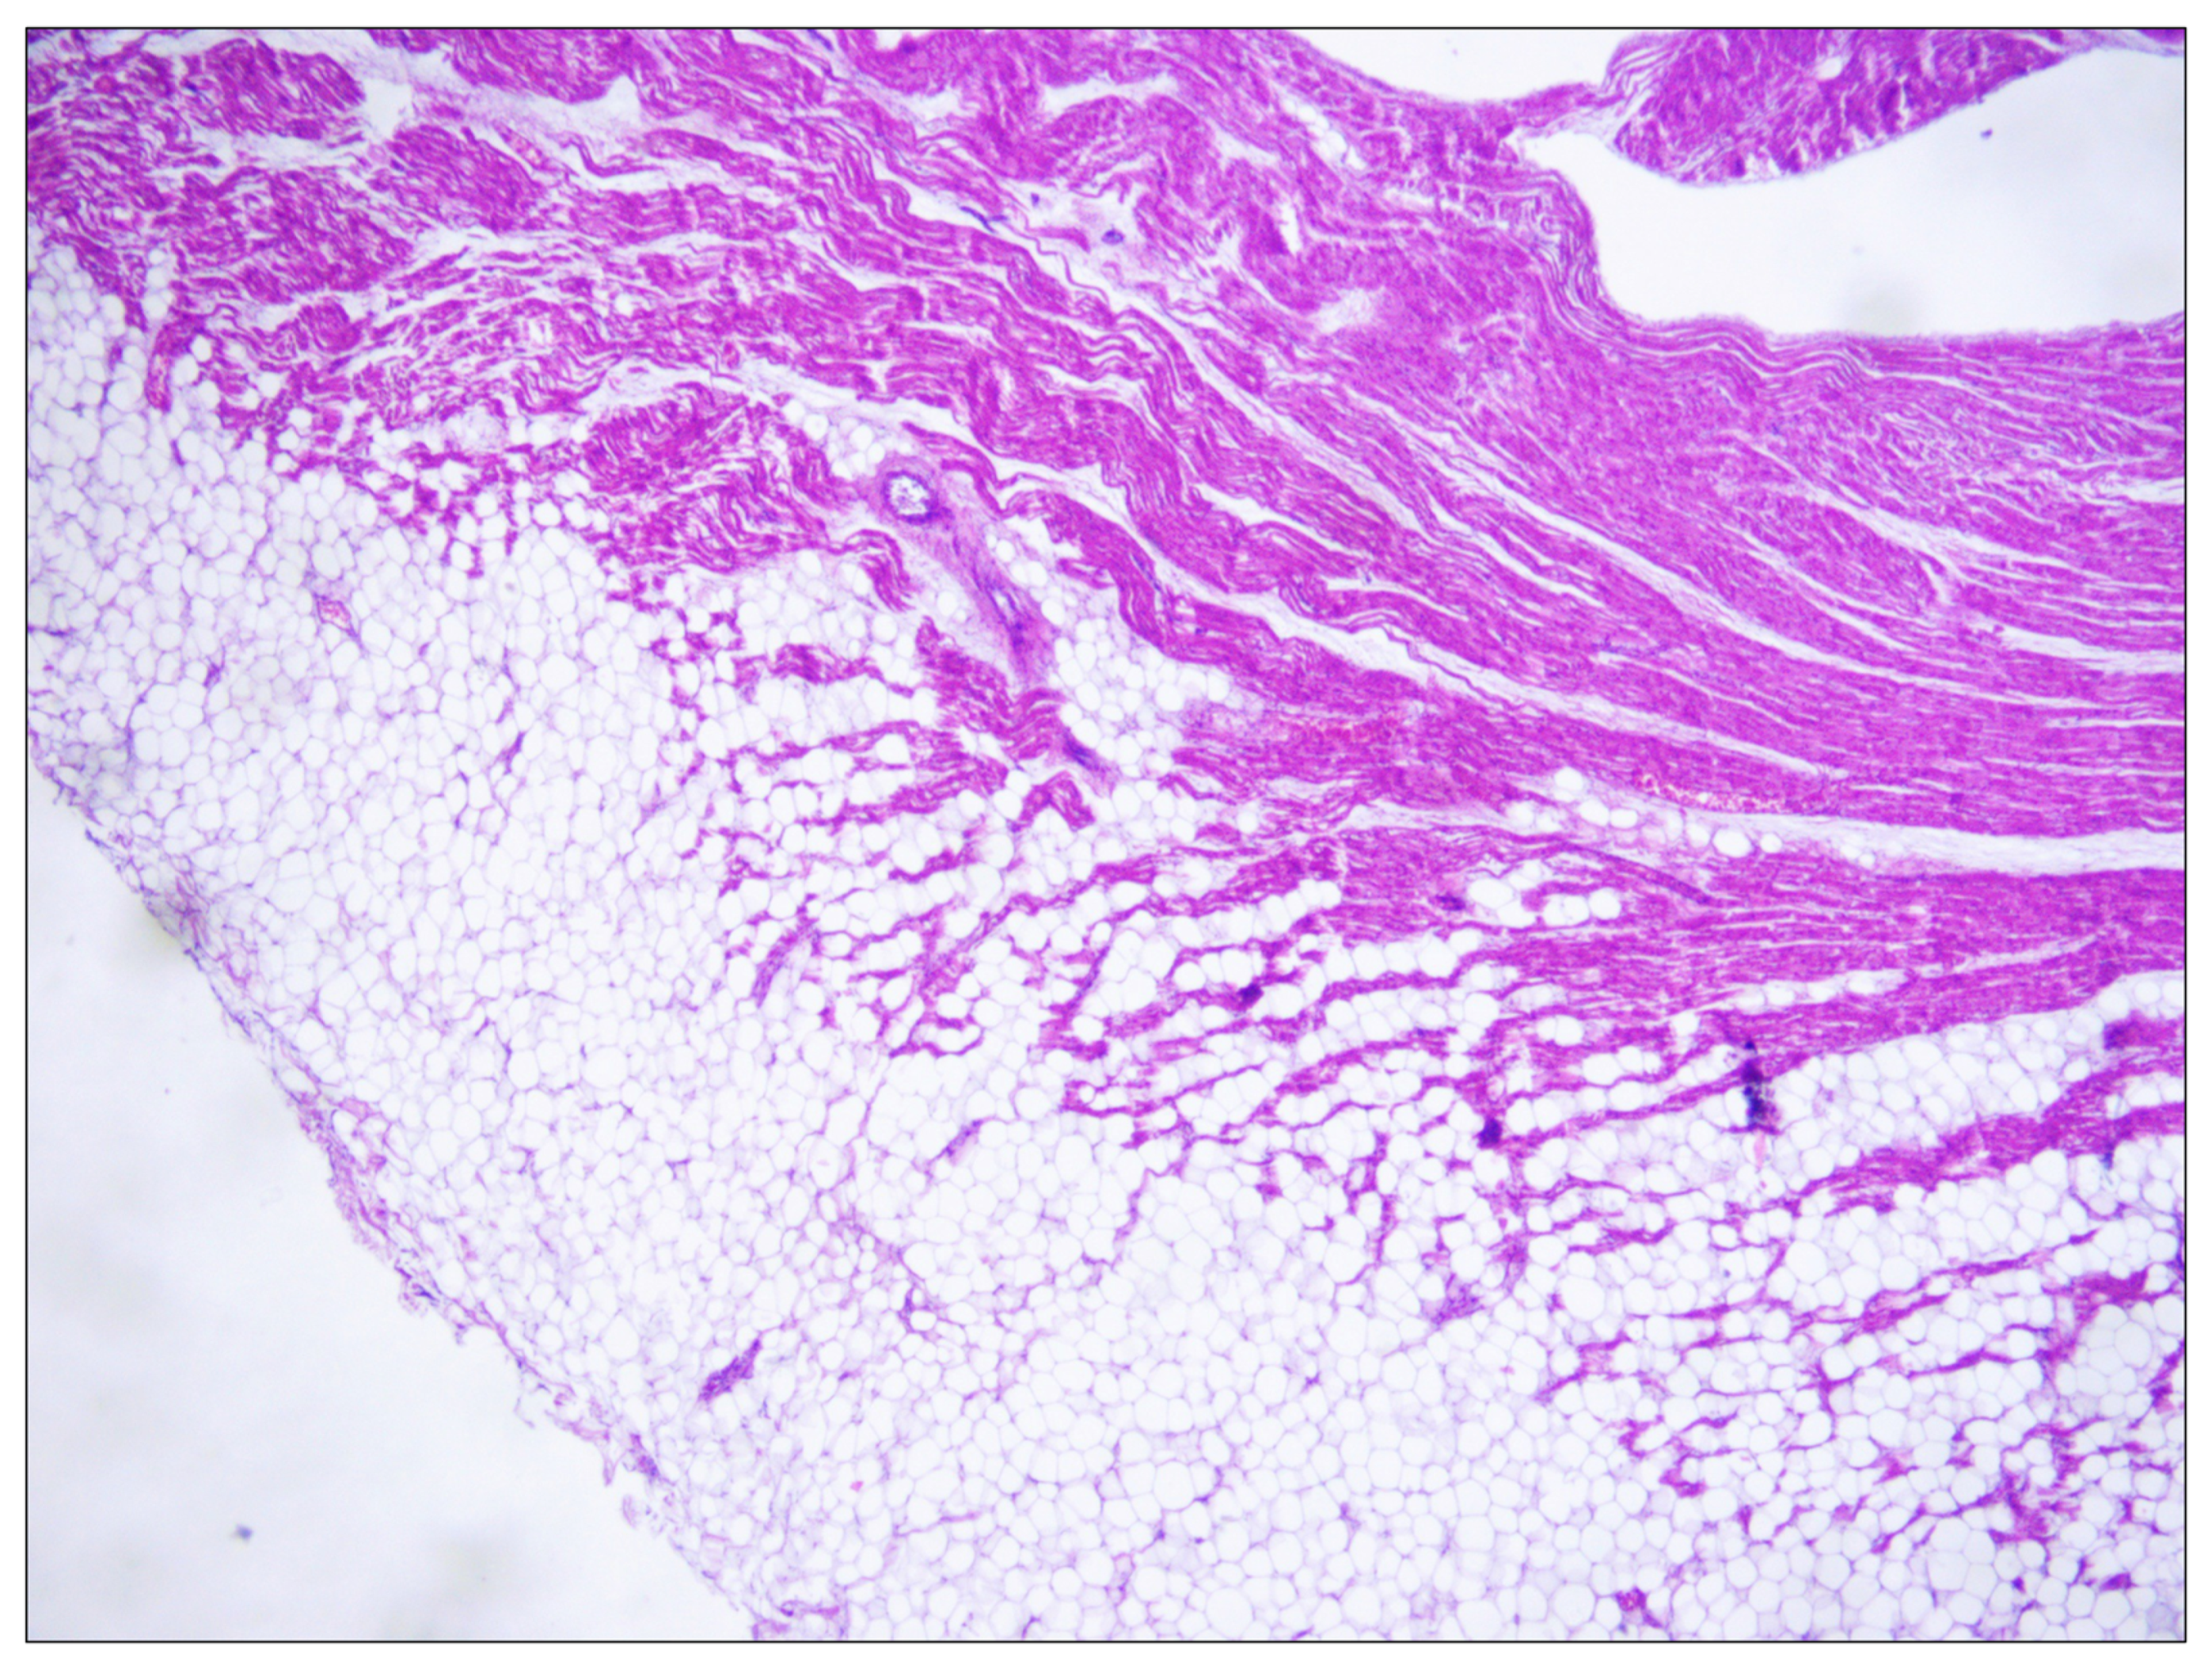

2. Cases Presentation